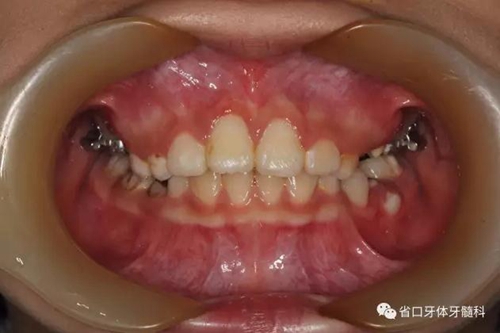

檢查:替牙列,12、21已萌出,11、22未萌,12、21間隙約5mm,右上前牙區(qū)前庭溝處見(jiàn)黏膜隆起,11牙冠未破齦。

口內(nèi)情況:正面觀